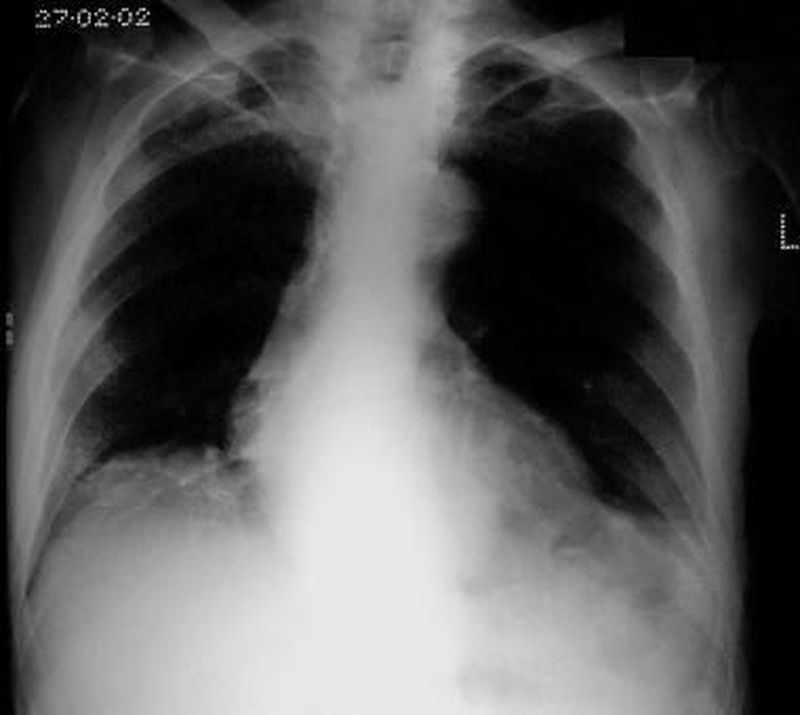

What is your diagnosis??????

Mediastinal adenopathy?

Cardiomegaly, ascitis?